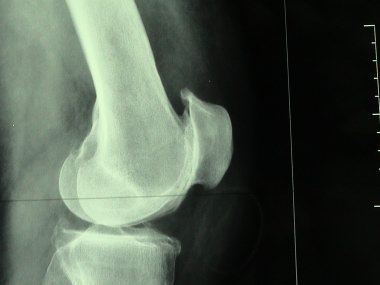

J'ai même la radio pour confirmer x)

arthrose du genou .jpg

arthrose du genou .jpg (12.75 Kio) Vu 932 fois

Soit dit en passant on identifie très clairement l'arthrose ! (chui médecin la ! :lol:)